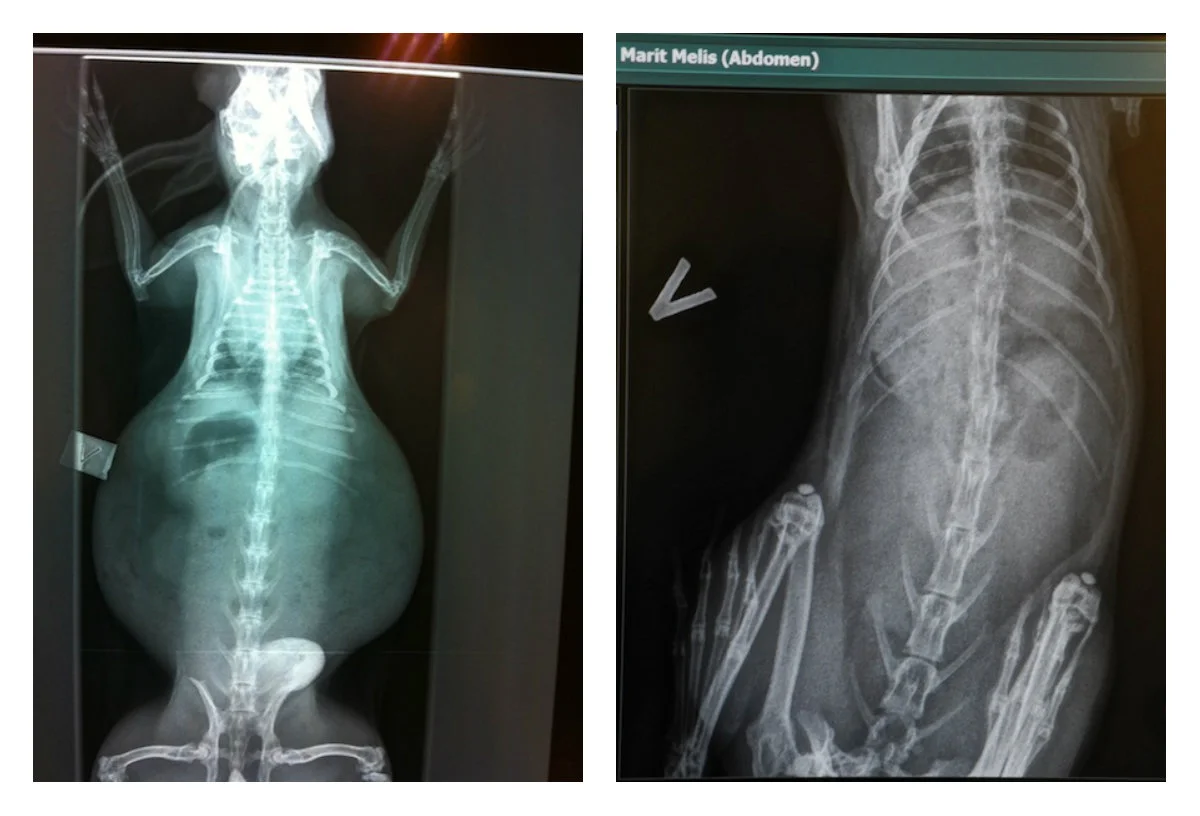

Billeder af Erling og Melis viser tydelige forskelle på bur kaninen og en frisk og rask kanin.

Røntgenbilder afslørede fremskreden arthrose og spondylose i ryghvirvlerne, samt forkalkninger i begge knæ og lidt i hofterne. Han havde derudover en del tandfejl som blev forsøgt justeret, samt meget kalcium i blæren. Alle disse plager har sandsynligvis påført ham smerter og ubehag i flere år. Erling havde også store klumper som i ser tydeligt på røntgenbillederne. Det virker så ekstremt, at det kunne vært et alvorligt tilfælde af brok, men han var imidlertid blevet deform grundet manglende muskulatur. Han havde ingen støtte muskulatur som kunne holde maven på plads, og den var som en konsekvens udflydende. Det som ser ud som en udefinerbar masse, er altså tarm og mave som buler ud. Der hvor billederne af Melis viser en stram og slank kanin i god form, ser Erling mere ud som en påkørt frø. De fleste vil ikke se og reagere på røntgenbilder af forkalkning i rygraden, mens billederne af Erling altså fik hele landet til at reagere. Erling blev en national berømthed, og nåde også ud til Sverige og Danmark med sin historie.

Se forskellen! Hos Erling holdes maven og tarmene ikke på plads, mens Melis er frisk og fin.